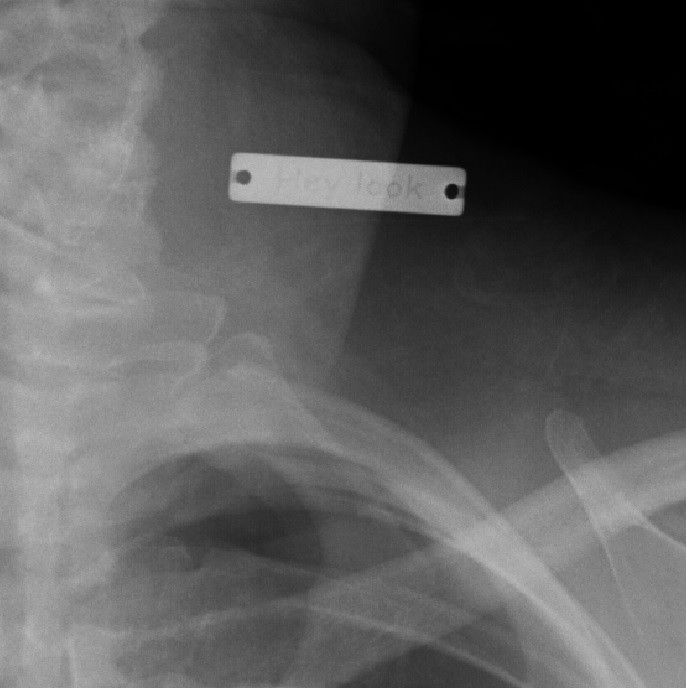

"Доктор удивился, увидев рентген"

А что здесь?